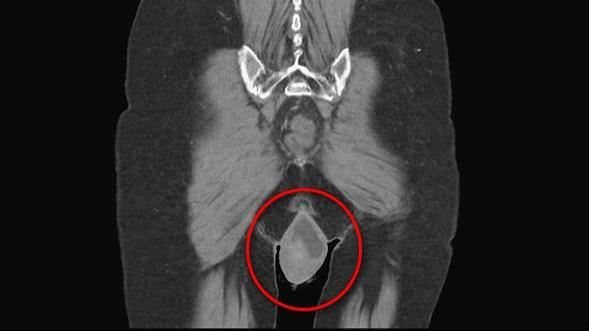

▲劉太太下體脫垂近20公分。(圖/台中醫院提供)

不敢相信!婦人走路走到一半陰道竟「掉出20公分」。台中一名70歲劉姓婦人患有失智症,且有肝硬化導致腹腔壓力過大,因此讓骨盆腔中的陰道脫垂,露出體外近20CM,她也因此感到不適、走路常覺得「卡卡」,經醫師檢查後也發現她因脫垂,子宮也有發炎與糜爛的症狀。好在醫師建議下,透過「棘韌帶懸吊術」手術,改善骨盆腔與陰道脫垂問題,劉姓婦人才能行動自如。

台中醫院婦產科醫師林新旺表示,會導致骨盆腔脫垂,是因為骨盆腔肌肉鬆馳,「扶不起」骨盆腔裡如子宮、膀胱、陰道等等器官,導致滑脫出體外。再加上這名婦人患有輕微失智,且有肝硬化的問題,當時的健康狀況並不是很理想,「她本身有腹水、肺積水的症狀,雖然還能走,但因為脫垂的關係,行動比較不靈敏。」由於內科疾病帶來的腹部積水症狀,會讓腹腔壓力增加,再加上患者年紀較大使症狀特別嚴重。而婦人的老公看到其下體脫垂近20公分,並出現子宮發炎等現象,使他相當心疼,不斷央求醫師盡速讓妻子開刀手術,讓他相當動容。